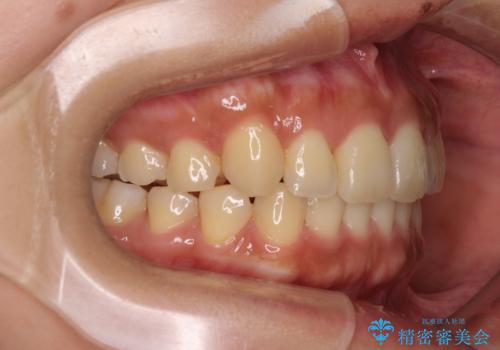

【モニター】歯列が狭くデコボコが気になる 急速拡大装置を用いたインビザライン矯正

- 奥歯の咬み合わせと治療を放置したまま奥歯を気にして来院された患者様です。

上顎骨の幅が下顎骨よりも小さいので、拡大装置により骨幅を広げて上下関係を改善し、その後インビザラインにて歯並びを整えることとしました。

上下の骨幅を改善したことで、スムーズに歯列矯正を行うことができました。

土台のまま放置されていた歯は土台の状態で咬み合っていましたが、急速拡大を行った際に咬み合わせが著しく挙上されたため、その際に土台を大きくすることで咬み合う歯との距離を確保しました。